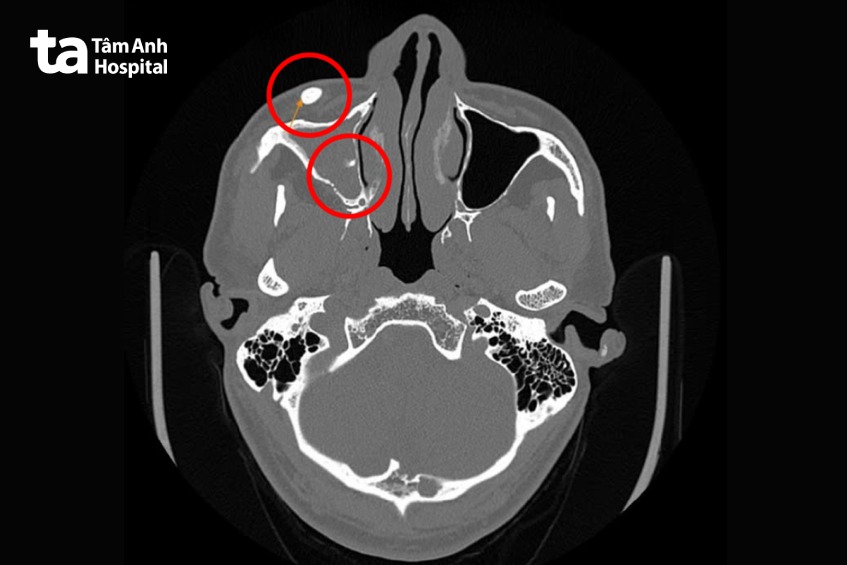

Kết quả nội soi tại Trung tâm Tai Mũi Họng ghi nhận mũi xoang phải ông T. phù nề, khe giữa mũi xuất tiết dịch nhầy mủ, vẹo vách ngăn sang phải. Kết quả chụp cắt lớp vi tính (CT-scan) ghi nhận xơ vữa vôi hóa hai bên đoạn xoang hang và đoạn mắt, dày niêm mạc và dày thành xoang hàm phải, có vài vị trí khuyết thành trước xoang hàm phải, nghi viêm xoang mạn tính, khả năng do nấm, phì đại cuốn mũi dưới hai bên. Viêm xoang do nấm là tình trạng viêm xoang với sự hiện diện của nấm trong các hốc mũi xoang, gây viêm nhiễm kéo dài. Nấm có thể phát triển thành khối đầy trong xoang, phá hủy các thành xoang, sau đó xâm lấn những cơ quan lân cận như hốc mắt, sọ não.

Kết quả chụp CT cũng ghi nhận, cấu trúc đậm độ cao trong mô mềm vùng má phải, kèm vài nốt vôi nhỏ xung quanh và phù nề mô mềm quanh vị trí này.

GS.TS.BS Trần Phan Chung Thủy, Cố vấn Trung tâm Tai Mũi Họng, Bệnh viện Đa khoa Tâm Anh TP.HCM chẩn đoán ông T. viêm đa xoang nhầy mủ, dị vật phần mềm vùng má và dị vật xoang hàm.

GS Chung Thủy giải thích, dị vật này là một vật thể nhỏ nằm trong mô mềm ở má phải. Ngoài ra, xung quanh xoang hàm phải còn xuất hiện một số nốt cản quang giống kim loại, sưng viêm, phù nề – dấu hiệu của phản ứng lâu dài của cơ thể với dị vật. Xoang hàm là các hốc xoang nằm ở hai bên gò má và hốc mắt. Tình trạng viêm xoang hàm đã lan rộng, ứ dịch và phù nề mô mềm nên gây sưng mắt, sưng mặt.